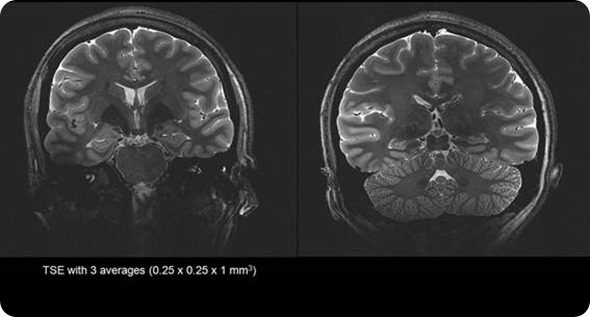

Stronger magnet fields increase the signal-to-noise ratio of the MRI signal. This increase in signal to noise can then be used to increase the spatial or temporal resolution of the image. Simply put, the higher the magnetic field strength, the more detail we can see inside the body.

Most MRI scanners operate between 1.5 Tesla and 3 Tesla.  Due to benefits of the increased resolution at higher filed strengths SMT have developed a ground breaking 7 Tesla system, the MAGNETOM Terra. This new system has been designed to meet the demands of both researchers and clinicians.

Due to the extra signal to noise available at 7 Tesla we are able to generate exquisite image quality to show vascularity of the brain without the need for an injection of contrast media often required at lower field strengths.